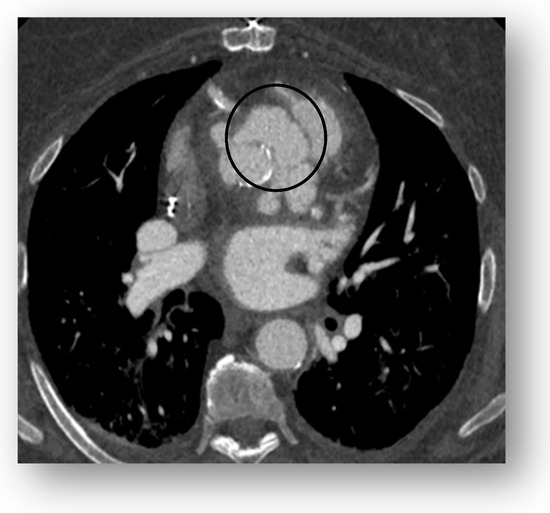

Multimodality Imaging in Infective Endocarditis: A Clinical Approach to Diagnosis

by Leonardo Brugiatelli, Francesca Patani, Carla Lofiego, Martina Benedetti, Irene Capodaglio, Pongetti Giulia, Francioni Matteo, Paolini Enrico, Nazziconi Marco, Kevin Maurizi, Furlani Giulia, Massari Arianna, Luciani Simone, Anselmi Benedetta, Gatti Chiara, Schicchi Nicolò, Fogante Marco, Tarsi Giovanni, Dello Russo Antonio, Di Eusanio Marco, Marini Marco and Fabio Vagnarelliadd Show full author list remove Hide full author list

Medicina 2025, 61(12), 2241; https://doi.org/10.3390/medicina61122241 - 18 Dec 2025

Infective endocarditis (IE) is a life-threatening condition with a rising incidence, demanding rapid and precise diagnosis. While echocardiography remains the cornerstone of initial evaluation, its limitations in complex cases—such as those involving prosthetic valves or cardiac devices—are well-known. This review synthesizes current evidence [...] Read more.

Infective endocarditis (IE) is a life-threatening condition with a rising incidence, demanding rapid and precise diagnosis. While echocardiography remains the cornerstone of initial evaluation, its limitations in complex cases—such as those involving prosthetic valves or cardiac devices—are well-known. This review synthesizes current evidence and guidelines to outline a practical, multimodality imaging approach for IE. We emphasize that integrating advanced techniques like cardiac computed tomography (CT) and [18F]-fluorodeoxyglucose positron emission tomography/computed tomography (FDG PET/CT) early in the diagnostic pathway, particularly in high-risk scenarios, significantly enhances diagnostic certainty, guides therapeutic decisions, and improves patient outcomes. A tailored imaging strategy, driven by clinical presentation and integrated within a multidisciplinary endocarditis team, is paramount for modern IE management. Full article

(This article belongs to the Special Issue Diagnosis and Treatment of Valvular Heart Diseases)

Show Figures

Figure 1